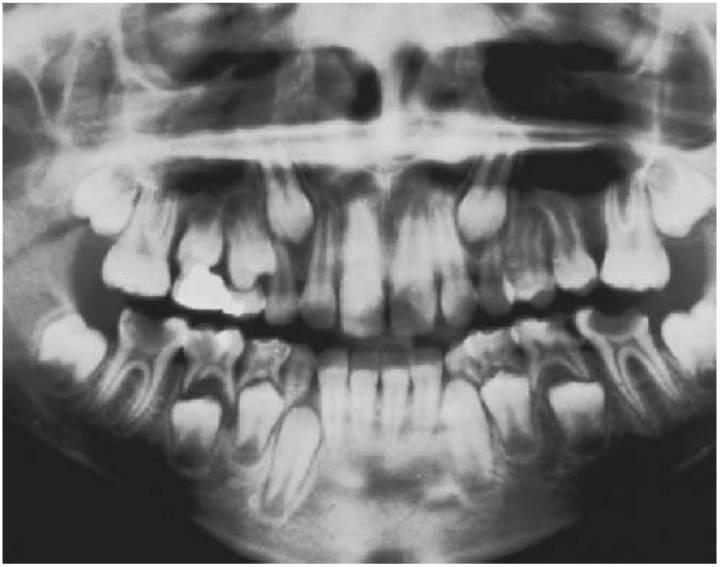

- Radiografía panorámica: proporcionará una imagen total de la dentición y del maxilar y la mandíbula en desarrollo. Se trata de la radiografía estándar utilizada en la valoración ortodóncica, si bien pueden requerirse imágenes adicionales para permitir un análisis más detallado de la anomalía sospechada.

Diagnóstico

El conocimiento de la secuencia normal y de la edad media de erupción de los dientes permanentes alertará al facultativo de la posibilidad de una ausencia congénita. Debe investigarse con radiografías cualquier retraso temporal en la erupción normal de los dientes permanentes o en la exfoliación de los dientes temporales. La ortopantomografía (OPG) proporcionará la mejor imagen para la investigación de los premolares y molares, si bien no suele ser clara en la región de los incisivos debido al estrecho pasillo focal. Puede requerirse complementarla con imágenes periapicales o bien con una imagen oclusal anterior en el maxilar.

Para la mayoría de los niños, una revisión radiográfica a la edad de 7 años mostrará la presencia o ausencia de todos los dientes permanentes excepto de los terceros molares. Se debe señalar que existe una gran variación sobre todo en la zona del segundo premolar y que, aunque los terceros molares no suelen ser visibles en las radiografías antes de los 9 años de edad, la radiografía sí mostrará el folículo dental antes de que comience la calcificación. Por último, existe un intervalo de tiempo de desarrollo entre la presentación del folículo y el comienzo de la calcificación, sobre todo en los segundos premolares.